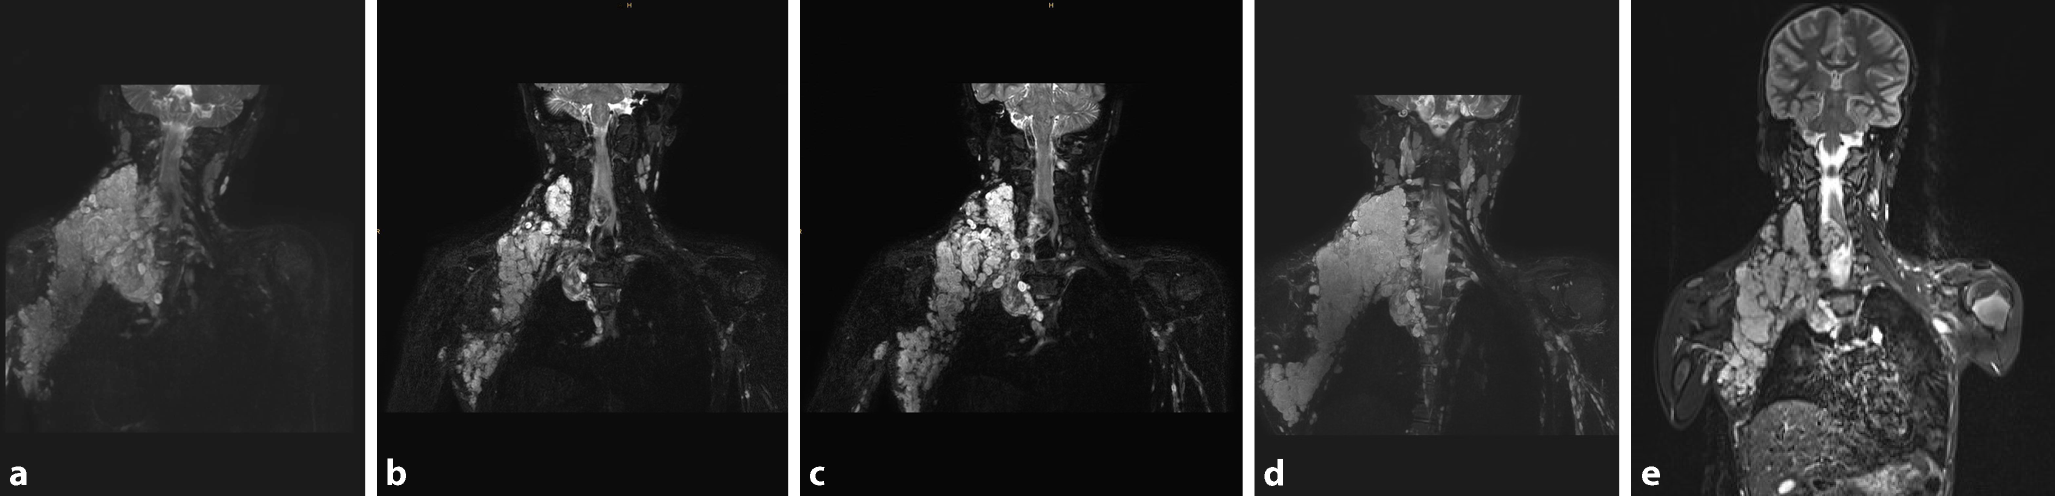

Abb. 3

MRT von Patient 2 mit ausgedehntem plexiformem Neurofibromen entlang des Plexus brachialis rechts. a Vor Therapie mit MEK-Inhibitor. b Nach 2 Jahren Therapie (Größenreduktion wurde erreicht). c Nach 3 Monaten Therapiepause (deutlicher Progress ersichtlich). d Weiterer Progress nach erneutem Therapiestart mit MEK-Inhibitor. e Erneutes, jedoch verzögertes Ansprechen unter weiterer Therapie. (© A. Azizi)

Bei Adrian (Name geändert) wurde bereits im Kleinkindalter die Diagnose einer Neurofibromatose Typ 1 gestellt. Bereits ab Geburt bestand eine sehr ausgedehnte Raumforderung im rechten Halsbereich. Eine Teilresektion im frühen Kindesalter ergab die Diagnose eines plexiformen Neurofibroms (PN), der Tumor habe jedoch im Verlauf an Größe zugenommen. Die Vorstellung in unserer Ambulanz erfolgte im Alter von 7 Jahren mit der Frage einer möglichen erneuten Operation. In der neurologischen Untersuchung des Patienten fiel auf, dass er rechtsseitig einen erheblichen Schultertiefstand und eine distale Kraftminderung der oberen Extremität aufwies. Zudem gab der Patient intermittierend Schmerzen und ein Kribbelgefühl sowie eine Hypästhesie im Bereich der Hand an. Zur weiteren Diagnostik erfolgte eine gezielte MRT-Untersuchung des Plexus brachialis, in der sich ein Konvolut aus plexiformen Neurofibromen im Bereich des Nervenplexus zeigte, die sich auch in den Spinalkanal drängten und zu einer massiven Verlagerung und Kompression des Myelons führten (Abb. 3a).

Adrian hat die Therapie mit Selumetinib bisher gut vertragen, und es ist zu keinen erheblichen Nebenwirkungen gekommen (oft neigen Patient*innen zu Hautausschlägen, asymptomatischem CK-Anstieg, gastrointestinalen Symptomen, von denen unser Patient verschont blieb). Er erhält regelmäßige MRT-Kontrollen die in unserem interdisziplinären NF-Board besprochen werden. Wenngleich das zervikale plexiforme Neurofibrom sich zwischen den einzelnen Bildgebungen stets stabil zeigte, so konnte man im längerfristigen Verlauf eine Reduktion erkennen (Abb. 3b). Das Ansprechen unter Selumetinib tritt oft erst langsam und manchmal auch erst nach mehreren Monaten auf. Sehr schnell (innerhalb weniger Wochen) verschwanden unter Therapie jedoch die neurologischen Beschwerden, wie z. B. Schmerzen oder Gefühlsstörungen und zu einem Teil auch die Kraftminderung. In der neurologischen Untersuchung fällt eben weiterhin die Reduktion der Kraft in der oberen Extremität auf, welche sich laut dem Patienten im Alltag nicht auswirke. Da sich der Befund schließlich lange Zeit stabil zeigte, erfolgte im Sommer 2022 ein Auslassversuch der Medikation. Leider kam es binnen weniger Monate zu einer Größenprogredienz des plexiformen Neurofibroms, und der Patient war wieder schmerzgeplagt, weshalb die Therapie wieder aufgenommen werden musste (Abb. 3c). Dies resultierte in einem erneuten sofortigen klinischen Ansprechen bzgl. der Dysästhesie, und das PN stabilisierte sich (Abb. 3e). Aktuell ist daher geplant, dass die Behandlung bis auf Weiteres fortgeführt werden soll. Die optimale Therapiedauer für inoperable plexiforme Neurofibrome wird sich erst in den nächsten Jahren bei zunehmender Erfahrung mit dieser Wirkstoffklasse zeigen. Auch werden wir erst durch Follow-up-Studien mögliche unbekannte Langzeitfolgen der Therapie (evtl. positive [Stichwort Kognition, Lebensqualität] oder u. U. auch negative) erfassen können [5, 6].